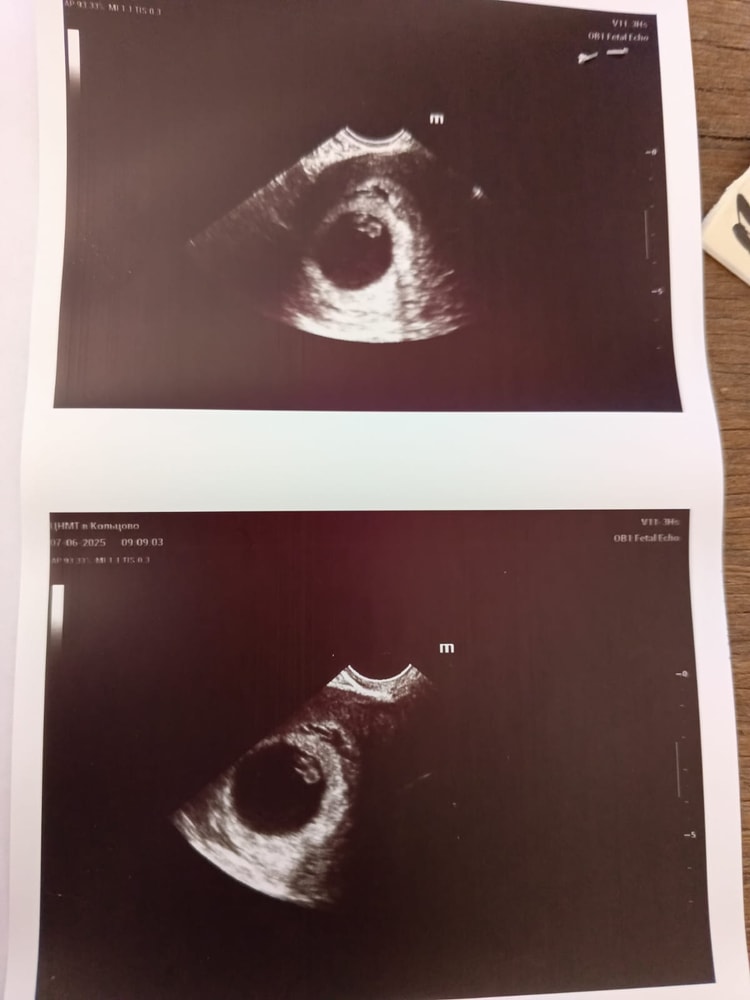

УЗИ ЖМ

Ой девочки, сейчас начала все внимательно читать по УЗИ, она мне написала желточный мешочек 16 мм, в прошлый раз был 5. Ну по фотке смотришь он бы тогда в половину ПЯ был( ПЯ 27,5) вообще уже ничего не понимаю, одни расстройства..Сейчас уже в ним не попаду, чтоб уточнить или уже думаю сидеть на попе ровно до недельки полторы и на учет вставать

Опечатка,нормальный жм по фото у вас